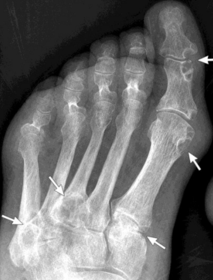

What disease is this? What indicates this? | Tophaceous gout. Soft tissue swelling surrounding the index finger PIPJ, with associated erosion and bone resorption |